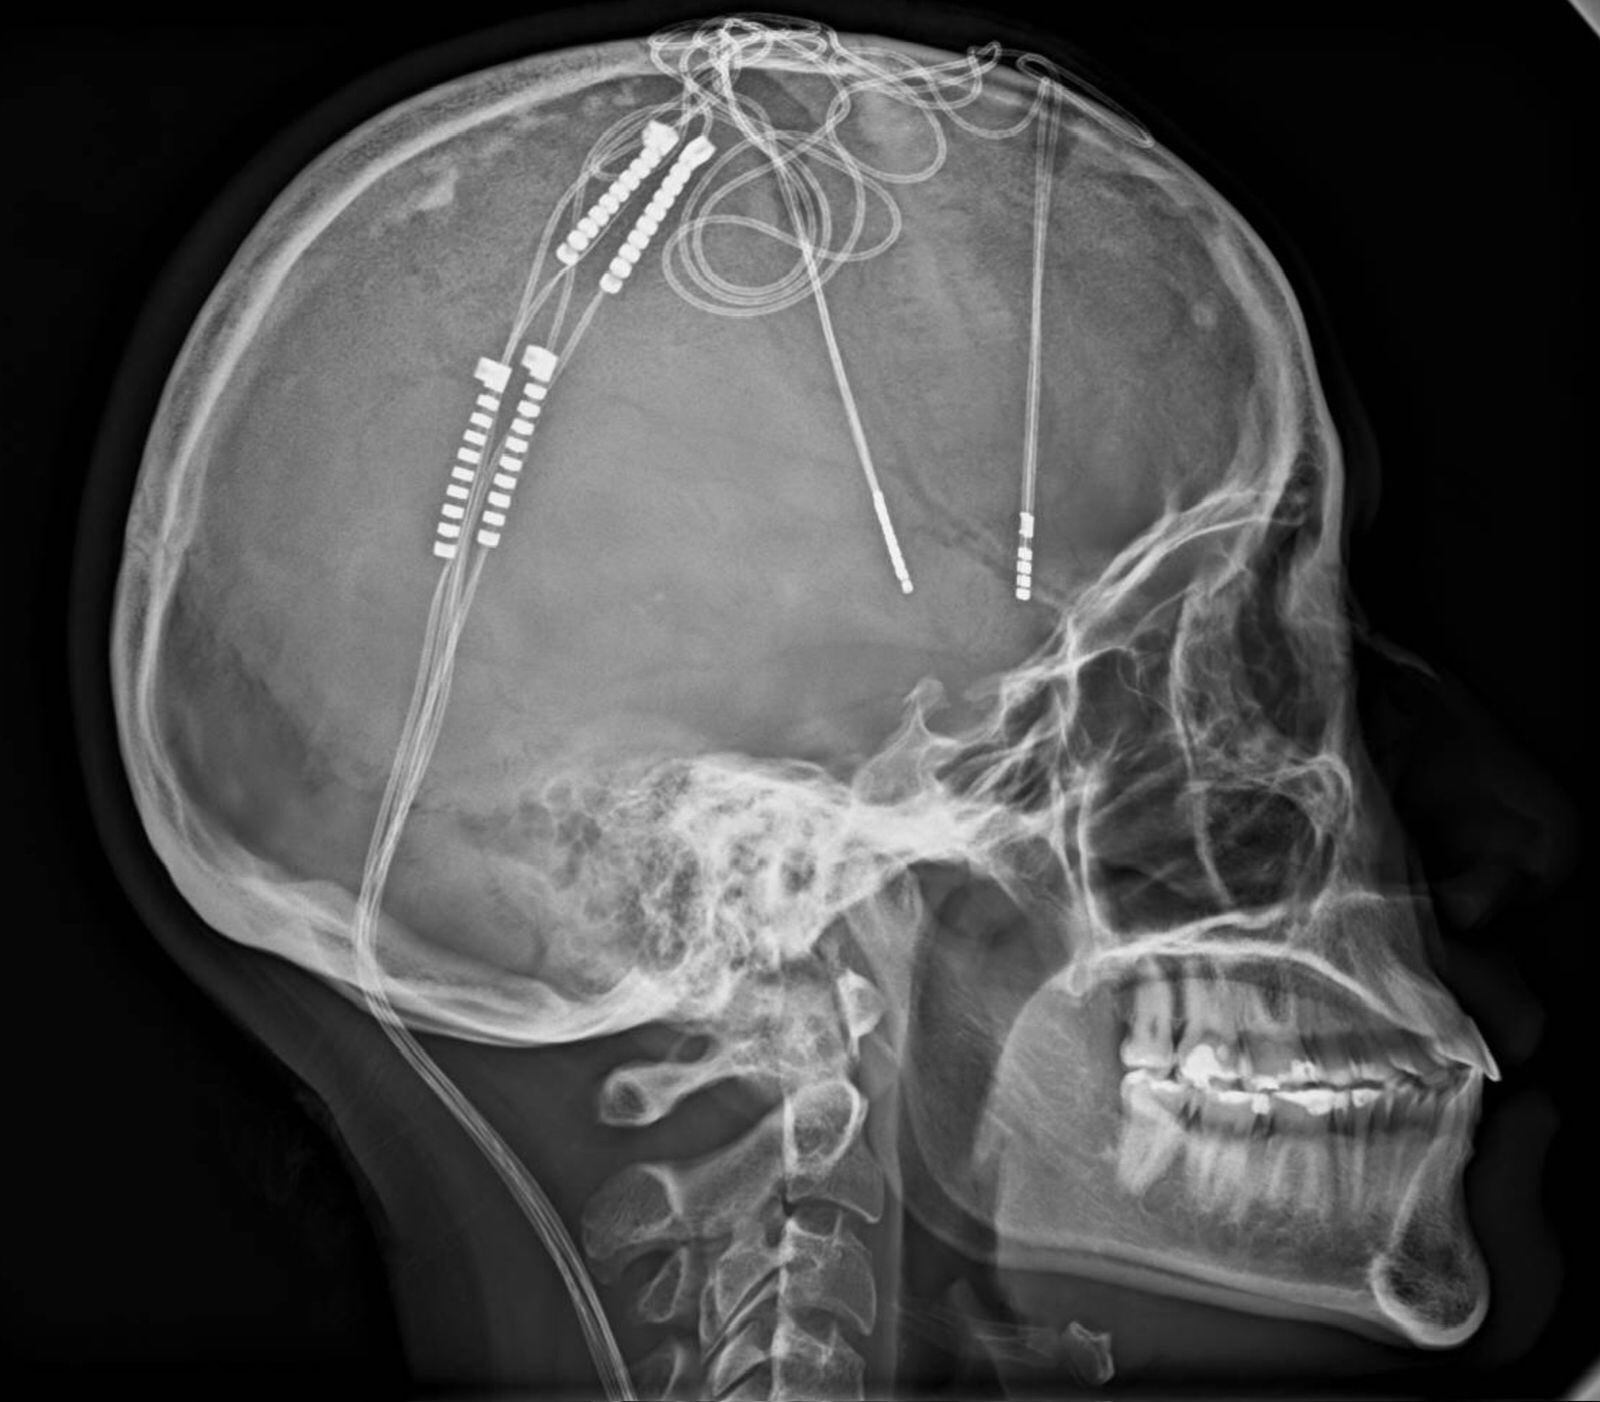

De acuerdo con el informe del centro médico, la intervención pionera fue dirigida por el doctor William Contreras, un neurocirujano colombiano que logró implantar cuatro electrodos en el cerebro de Lorena Rodríguez.

El objetivo era estimular de forma constante el sistema límbico, área cerebral clave en la regulación de las emociones. Este procedimiento, considerado una cirugía de alta complejidad, busca mejorar la condición de la paciente tras agotar otras opciones terapéuticas sin obtener resultados duraderos.

El procedimiento consistió en insertar cuidadosamente los electrodos y conectar los impulsos eléctricos a una batería ubicada debajo de la clavícula. “La batería de Lorena dura 25 años. Cuando se acabe, se reemplaza, pero los electrodos quedan de por vida”, detalló el doctor Contreras.